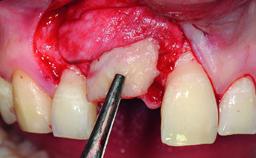

A 32-year-old female Caucasian patient with a compromised maxillary right central incisor was referred to us by a general dentist. Her chief complaints were discomfort and mobility of tooth 11 with unsatisfactory esthetics due to discoloration. The patient reported a previous trauma, some years earlier, as the origin of pathology on the afflicted tooth. Anamnesis was negative for any other dental or periodontal pathology in the remaining dentition. The patient did not take any medication and reported to be a light smoker (5–10 cigs/day). She had high esthetic expectations of her treatment. The extraoral examination revealed a high smile line with full exposure of her maxillary teeth and surrounding soft tissue in the area between the second premolars.

Bone Volume | Deficient horizontally, requiring prior grafting |